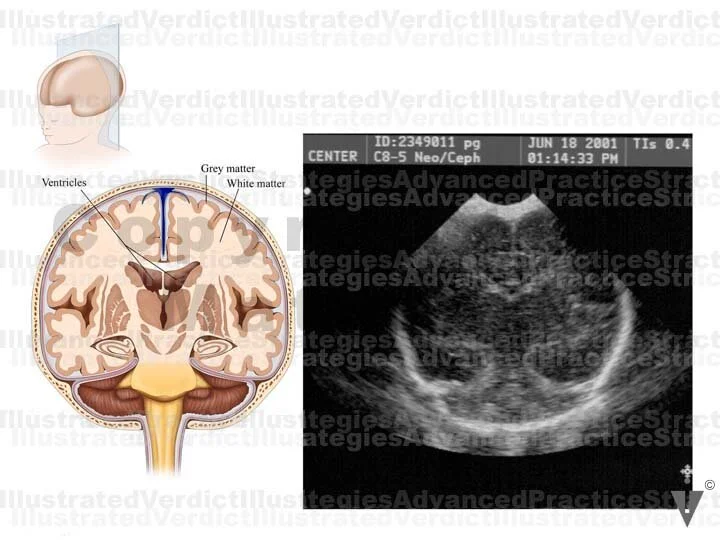

1. Orientation view

2. Coronal view of brain w/ ventricles

3. Coronal view Ultrasound